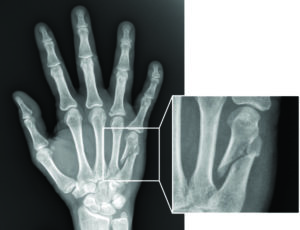

Однако, с целью постановки точного диагноза и определения разновидности перелома, пациентам назначается обязательное рентгенографическое исследование, позволяющее выявить все возможные сколы и смещения. Рентгеновский снимок делается в трех проекциях.

В случаях внутрисуставного, многооскольчатого перелома, может быть рекомендовано проведение компьютерной томографии или же магнитно-резонансной томографии.

Хирургические методы лечения назначаются при осложненных переломах со смещением и предполагают госпитализацию пострадавшего. В ходе операции через ногтевую фалангу пациента вводится специальная спица, способствующая скелетному вытяжению обломков.

В наиболее тяжелых случаях проводится хирургическое вмешательство под действием общего наркоза. Кисть разрезается, проводится вправление и сопоставление костных фрагментов. Специалист придает кисти и пальцам правильное положение, после чего вводится спица. В завершение операции накладываются швы и фиксирующая гипсовая повязка.